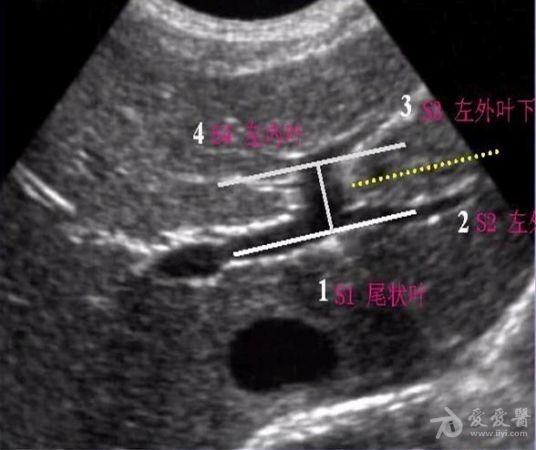

超声肝的分段解剖图片,肝超声分段解剖示意图

肝脏的分叶分段(解剖 超声声像图)

肝脏超声分段

肝超声分段解剖示意图

超声肝脏8分段法图谱